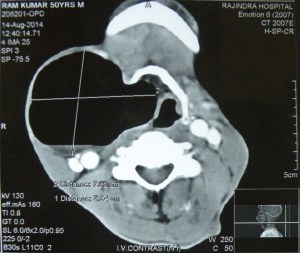

Repaired a large laryngocele for the first time in life!. Had never seen it actually before this one. An old man ( a chronic smoker) had been having a large swelling on the right side of the neck for a long time, and now had been experiencing some pain and hoarseness of voice. ENT examination revealed an internal component of the laryngocele too which had displaced the larynx to the left.